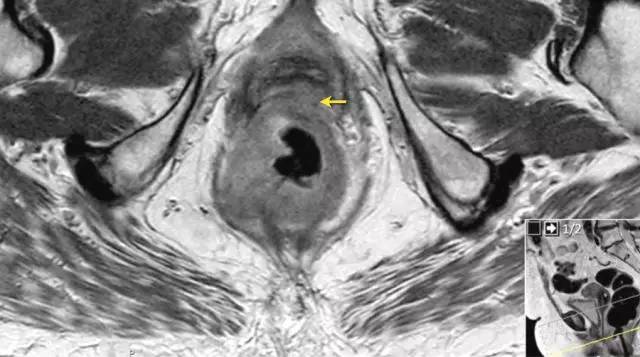

T3 分期

MRI 检测直肠周围组织浸润的敏感性为 82%,肿瘤侵犯或结缔组织增生反应均可表现为直肠周围浸润,为了避免分期不足,出现直肠周围浸润即作为 T3 期肿瘤。

T3 亚分期

基于英国 MRC 的 MERCURRY 研究所确立的标准,高分辨率 MRI 下,按照原发肿瘤突破肠壁固有肌层后侵入直肠系膜内的垂直距离来区分,按 1 mm,1~5 mm,6~15 mm,>15 mm 将 T3 分为 a、b、c、d 四个亚组。

低直肠肿瘤与阳性切缘率较高,局部复发率高,存活率差相关。这主要是由于解剖学考虑以及直肠系膜在此水平下降的事实。

有学者提出了一种低直肠肿瘤 T 分期。这种分期是基于冠状和轴向 T2 加权图像。